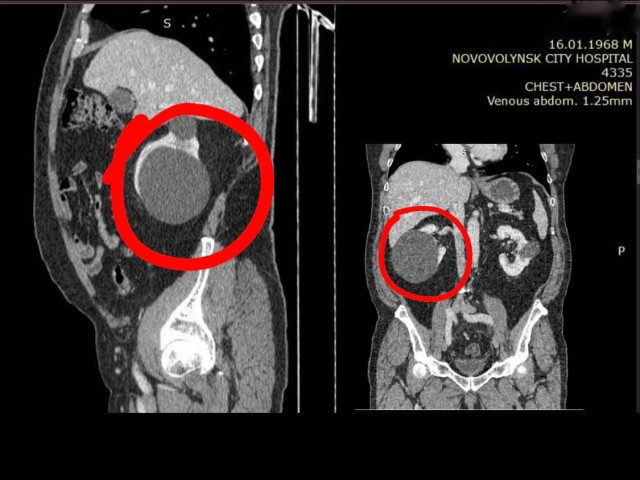

У волинській лікарні пацієнту видалили гігантську кісту нирки

У Нововолинській лікарні пацієнту видалили гігантську кісту усього через три проколи.

Кіста була особливо великих розмірів – 100 мм.

«Лапароскопічно видалили гігантську ксту нирки розміром 100 мм у три проколи.

Черговий пацієнт успішно прооперований командою наших лікарів: Ігорем Винницьким, Олегом Шипеликом та Іваном Мочерняком», – йдеться у дописі.